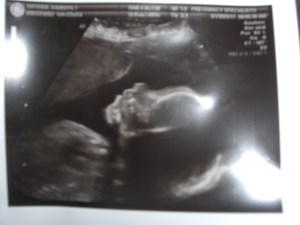

Baby K is looking good, weighing 1lb 7 oz putting her right where she should be. They couldn’t see the tear or any bleeding anymore…phew! I have been taken off restrictions for the most part. I can slowly start some low impact exercises like swimming, the stationary bike, walking and stretching but if I have any symptoms ie; cramping, contractions, fluid leaking ect. I have to stop. I am supposed to ease my way into this and then I will go back in 4 weeks to be checked out again. Looks like my teaching days are done for a while though. I guess it’s just too much “on my feet” and she called it a “strenuous” job, which is true.Â

The other thing she said was that I still had the Velamentous insertion and something called succenturiate lobed placenta which is when there is two parts of the placenta and one is significantly bigger than the other. The cord is running between the two. She didn’t give me much more info than that, just said they need to continue to monitor her growth. Scary how it’s always something when I go in for an exam! Next week I have my OBGYN appointment and a Gestational diabetes test. FUN!